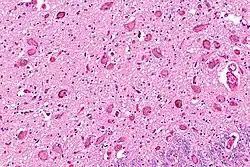

The locus coeruleus (LC) is located in the posterior area of the rostral pons in the lateral floor of the fourth ventricle. It is composed of mostly medium-size neurons. Melanin granules inside the neurons contribute to its blue colour. Thus, it is also known as the blue nucleus, or the nucleus pigmentosus pontis (heavily pigmented pontine nucleus).[5] The neuromelanin is formed by the polymerization of norepinephrine and is analogous to the black dopamine-based neuromelanin in the substantia nigra.

The locus coeruleus is affected in many forms of neurodegenerative diseases: genetic and idiopathic Parkinson's disease, progressive supranuclear palsy, Pick's disease, and Alzheimer's disease. It is also affected in Down syndrome.[29] For example, there is up to 80% loss of locus coeruleus neurons in Alzheimer's disease,[30] Mouse models of Alzheimer's disease show accelerated progression after chemical destruction of the locus coeruleus.[31] Neurofibrillary tangles, a primary biomarker of Alzheimer's disease, may be found in the locus coeruleus decades before any clinical symptoms.[32] The norepinephrine from locus coeruleus cells in addition to its neurotransmitter role locally diffuses from "varicosities". As such it provides an endogenous anti-inflammatory agent in the microenvironment around the neurons, glial cells, and blood vessels in the neocortex and hippocampus.[18] It has been shown that norepinephrine stimulates mouse microglia to suppress Aβ-induced production of cytokines and promotes phagocytosis of Aβ.[18] This suggests that degeneration of the locus coeruleus might be responsible for increased Aβ deposition in AD brains.[18] Degeneration of pigmented neurons in this region in Alzheimer's and Parkinson's disease can be visualized in vivo with Neuromelanin MRI.[33] Since the marked degeneration of locus coeruleus, and the neuroprotective properties of noradrenaline, Ian Robertson proposed the "Noradrenergic Theory of Cognitive Reserve" [34] which postulates that the upregulation of the locus coeruleus-noradrenergic system throughout the lifespan may enhance cognitive stimulation contributing to cognitive reserve preventing from neurodegeneration. Evidence appear to support this theory reporting the locus coeruleus integrity primarily responsible of biological brain maintenance,[35][36][37] including brain clearance,[38] cognitive efficiency, and reduced neuropathological burden.[35][39][40][41]